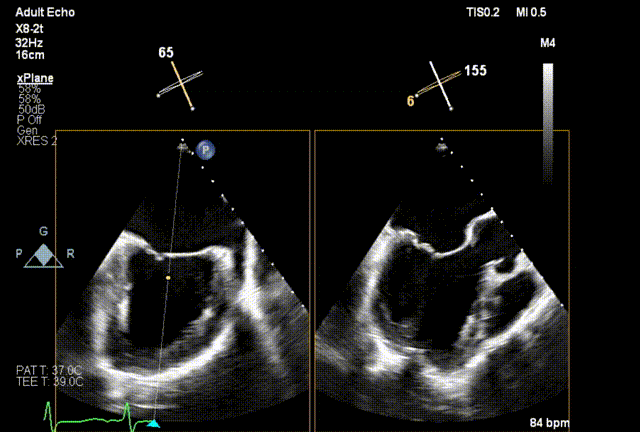

术前经食道超声(TEE)评估

术前3D

术前TEE

DMR P2脱垂连枷(脱垂范围:12mm,连枷间距:3mm),反流2区,MR重度(VC:4* 10mm),A2:21mm,P2:10mm,AP:30mm,MVA约 4.7 cm²。